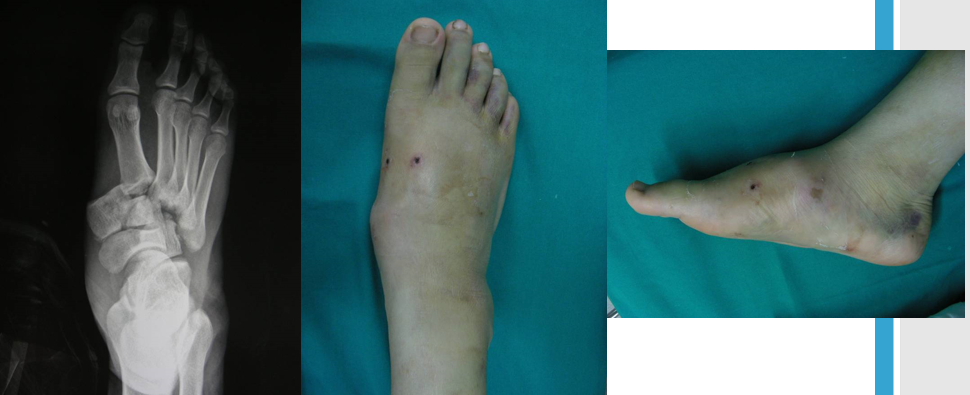

临床表现

中足疼痛、负重困难;足背肿胀;由于可能的自行复位可致畸形多变。

足底瘀青可出现较晚;跖跗关节局部压痛;轻度跖屈、背伸和旋转应力可显示不稳。

影像学诊断

在足正位X线上,第1、2、3跖骨的内外侧缘分别和它相对应的楔骨的内外侧缘呈一直线排列;第一、二跖骨基底间隙和内中楔骨间隙相等。

30°斜位上:1、第四跖骨内侧缘和骰骨内侧缘连续成一条直线2、第三跖骨内侧缘和外侧楔骨内侧缘连续成一条直线3、第二、三跖骨基底间隙和内、中楔骨间隙相等。

侧位上,跖骨不超过相应楔骨背侧缘。从远端的跖骨经过跖跗关节到近端的跗骨,应该是一条不间断的连线

2005年Pearse等提出“ABC”的方法来阅读足部X 线片, 以减少中、前足的漏诊。 A ( alignment)检查跖骨与相应楔骨的对应线 B ( bone)检查每一块骨的轮廓 C ( congruity )检查整体一致吻合, 在正位片上观察内柱, 在斜位片上观察中、外柱。侧位片的常规检查可发现Lisfranc关节矢状面的半脱位及撕脱性骨折